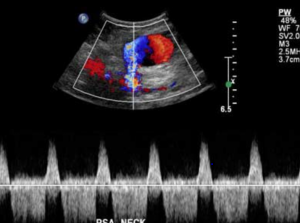

Esta complicacão se apresenta através de dor, hematoma e muitas vezes uma massa pulsátil no sítio de punção arterial, é uma complicacão que muitas vezes pode ser bastante séria, com risco de morte em caso de sua ruptura, sendo o diagnóstico precoce importante e realizado através da história, exame físico e uma ultrassonografia com Doppler da região.

A imagem de ultrassom acima mostra um pseudoaneurisma decorrente da artéria femoral profunda esquerda.